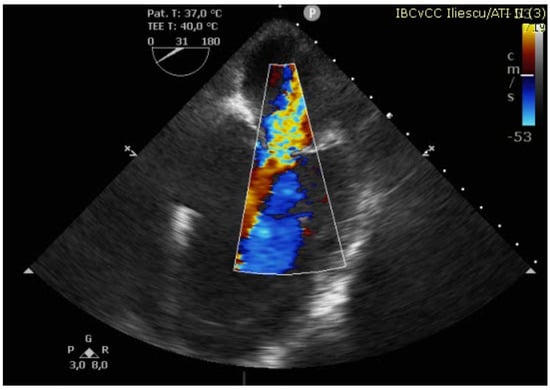

Figure 3. TEE showing large basal VSD.

The case was discussed in the multidisciplinary heart team (cardiologist, interventional cardiologist, cardiac surgeon, anesthesiologist) and, after informed consent, it was decided for a watchful waiting tactic, planning a delayed repair. Preoperatively, the patient was evaluated with a transesophageal echocardiography (TEE) for better defect characterization and MR quantification (Figure 3 and Figure 4). Percutaneous defect closure was deemed technically unfeasible due to the anatomy of the defect, which was located at the base of the septum and involved the mitral valve apparatus, while also exhibiting significant mitral valve regurgitation.